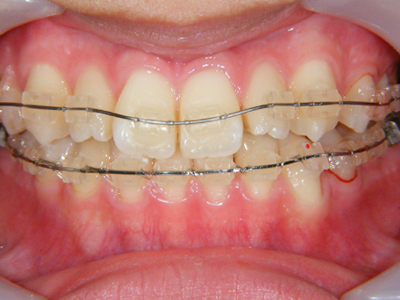

8. 矯正中正面

ジスキングには細心の注意を払い、矯正装置を装着したところです。ちなみに上顎の歯列拡大(少ししか拡大できなかったが)で、下顎左側の2,3番間の叢生が若干ですが改善しています。